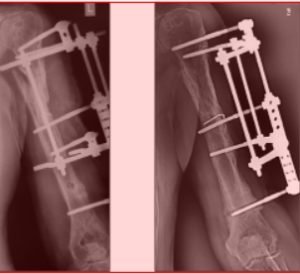

Клинический пример. БольномуЗ., 16лет, с диагнозом: закрытый диафизарный перелом костей правого предплечья со смещением фрагментов, - выполнена операция - остеосинтез АВФ стержневого типа (рис. 1,2).

После обработки операционного поля введены консольные стержневые фиксаторы путем ручного вкручивания в метафизарные и диафизарные отделы костей предплечья. Стержни закреплены с помощью кронштейнов во внешних опорах (рис. 3 - 7).